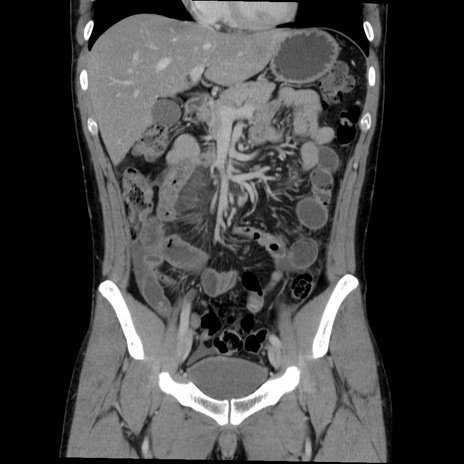

症例36(冠状断像)

【症例】20歳代 男性

【主訴】心窩部痛

【現病歴】今朝より上腹部痛あり。一旦軽快していたが再度出現したため救急要請。昨日夕に白身の魚を含む刺身を食べた。

【身体所見】BP 136/89mmHg、HR 74/min、BT 37.0℃、腹部:膨満、軟、心窩部に圧痛あり。反跳痛なし、筋性防御なし、腸雑音やや亢進あり。

【データ】WBC 17700、CRP 0.48